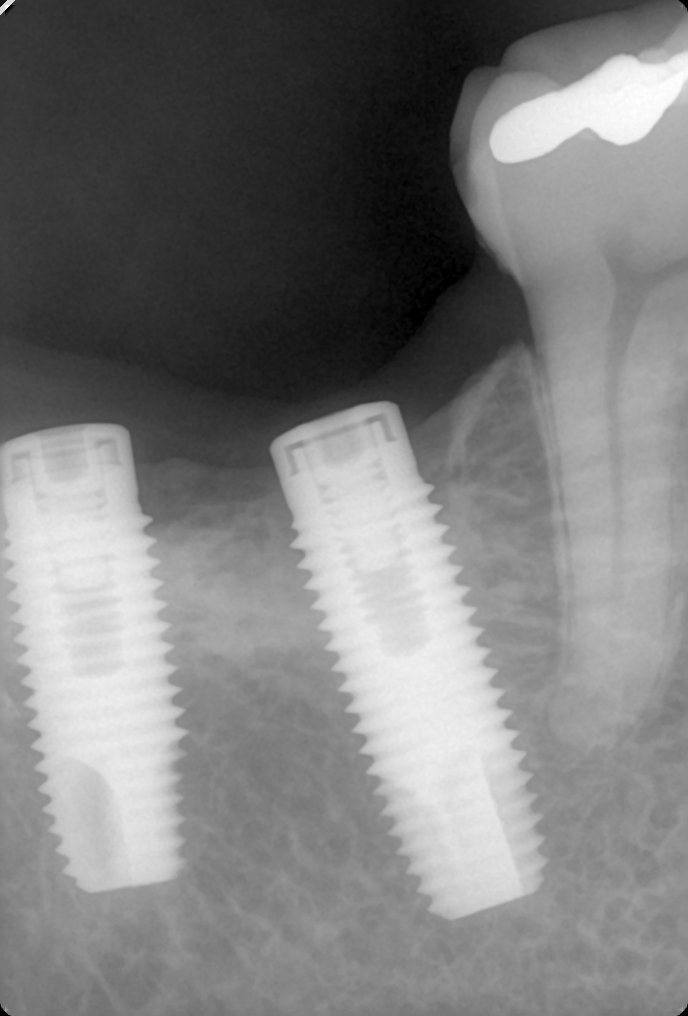

Le han puesto dos, en 47 y 48 pero el 48 no lo voy a rehabilitar. les agradecería conocer especificaciones del implante del 47 para poder rehabilitarlo gracias. son implantes [...]